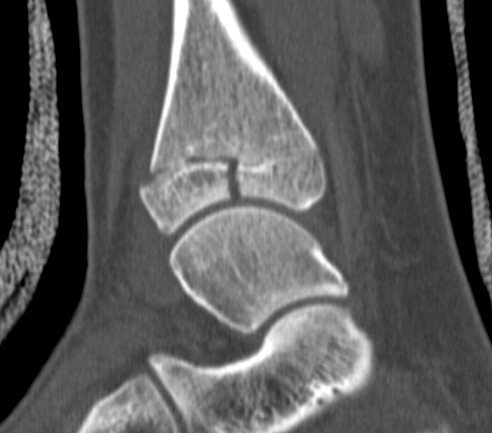

CT

Type III on coronal

Type II on sagittal

3 point star on axial

Triplanar Fracture

Definition

- fracture in coronal, sagittal and transverse planes

- 2, 3 or 4 part

Management

ORIF

- > 2mm displacement

- usually anterolateral approach to reduce

- epiphyseal medial-lateral screw

- metaphyseal AP screw

Complications

Growth arrest 10%